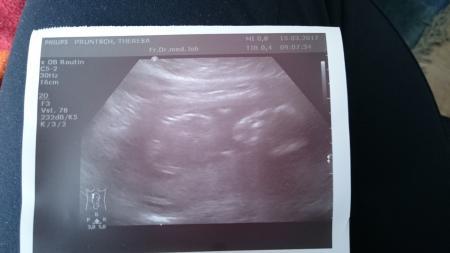

Huhu, wir waren ja heute auch dran. Wie beim letzten Mal war das Kind völlig tiefenentspannt und hatte die Hand am Kopf. Wir konnten zwar nicht viel sehen, aber es geht dem Baby gut da drin und es ist Ssl 11cm lang. Am 12.04. ist dann der nächste Termin mit Organscreening.

Bild zu Zurück vom FA - Forum für August - Mamis